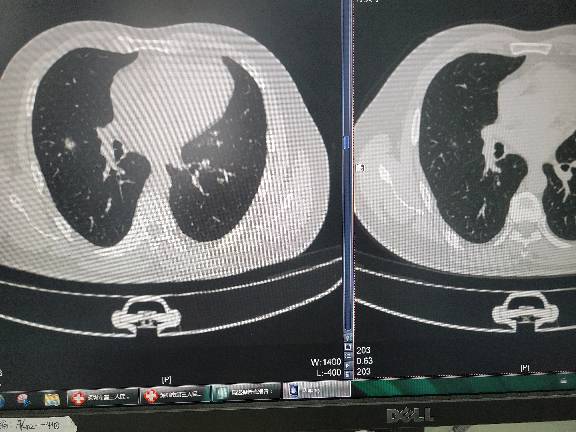

胸腔镜微创技术,尤其掌握非插管单孔肺癌根治术、肺段切除术等复杂胸外科手术,部分手术不需放置尿管、胸管,术后快速康复,缩短住院时间,部分手术24小时出院。 胸部结核病的外科治疗,包括肺结核、合并气胸、结核性脓胸、胸壁结核,术后大大缩短抗结核药物时间,减少肝功能损害的风险,减少结核病的复发。 营养不良的支持治疗,增加患者的食欲和体力,增加患者的免疫力,提高生活质量。 胸外科手术疑难杂症

男,副主任医师,医学博士,博士生导师为广州医科大学附属第一医院院长何建行教授。社会任职:ESTS member,广东省胸部肿瘤防治会理事,深圳市医学会消化病专委会营养支持学组副组长,深圳市抗癌协会肿瘤营养与快速康复委员会委员。能够熟练掌握胸腔镜微创技术,保留自主呼吸的非插管单孔胸腔镜技术,治疗早期肺癌、GGO、肺部孤立性结节、自发性气胸、结核性气胸、纵膈肿瘤、手汗症等常见病多发病。对结核病的外科治疗如慢性结核性脓胸、肺结核球、肺结核性空洞并曲菌球形成、支气管内膜结核、结核性毁损肺、胸壁结核有较深入的研究。对肺癌的化疗、靶向治疗,以及顽固性咳嗽的药物治疗、营养不良的支持治疗有丰富的临床经验。主持两项深圳市科技计划项目,发表国家级论文5篇。